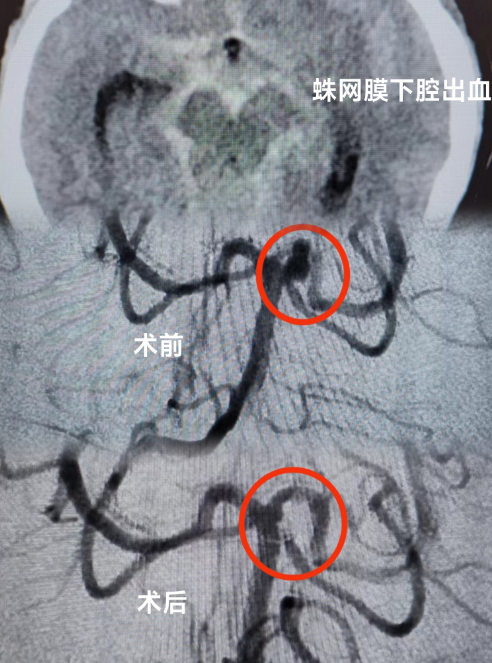

当天,患者被送到急诊科时,医生为她紧急安排头颅CT检查,发现患者有蛛网膜下腔出血的情况。蛛网膜下腔出血通常病情比较严重,可诱发脑血管痉挛,进而继发出现脑梗死,危害患者生命。为了帮助患者尽快脱离危险,急诊科立即联系了神经外科、重症医学科及心血管内科当班医生进行联合会诊。

小妲己直播app 多学科专家团队结合患者检查结果,认真分析患者病情,判断患者动脉瘤破裂出血可能性大,同时合并有急性冠脉综合征,不排除急性心梗的可能。考虑到患者病情的危重性及复杂性,专家团队建议患者入住重症监护病房(ICU),紧接着由神经外科医师团队运用神经介入技术为患者进行脑血管疾病诊治,同时神经外科医师与心血管内科介入医师通力合作,排查了心脏冠脉相关疾病。期间,麻醉科、重症医学科医师团队也全程为患者保驾护航,排查手术各种风险。

手术历经约3个小时,专家团队排除万难,为患者完成了全脑血管、冠脉造影术,以及颅内动脉瘤介入栓塞术手术,术后患者恢复良好。